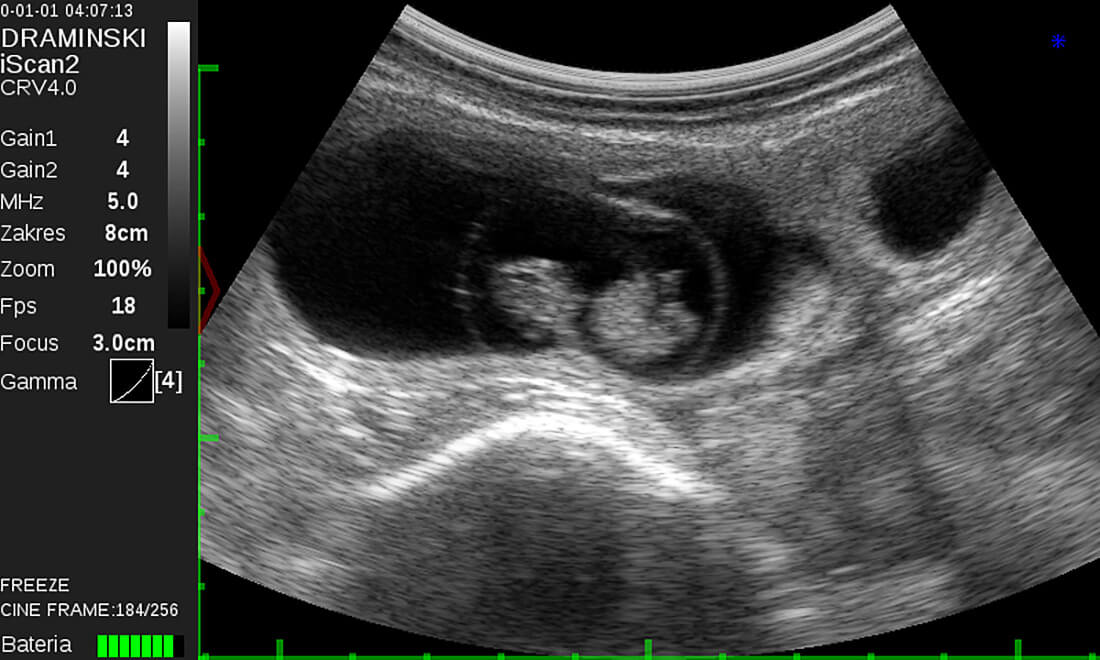

凸陣直腸探頭 用於馬、牛、豬及小型反芻動物的直腸檢查與腹部成像。亦可用於檢查肺部及生殖器官。